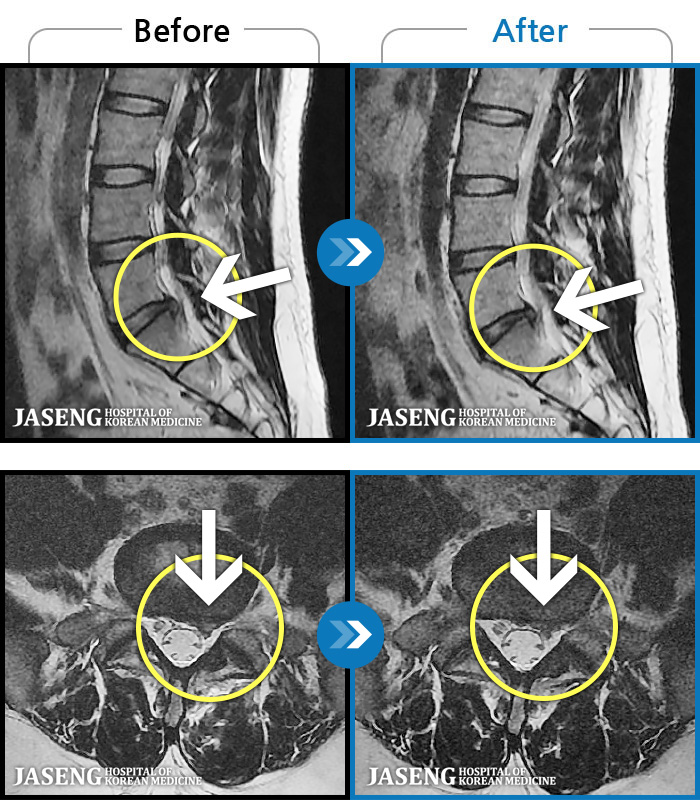

- MRI ġ

MRI ġ

1,299 MRI ũ ʸ Ȯϼ.